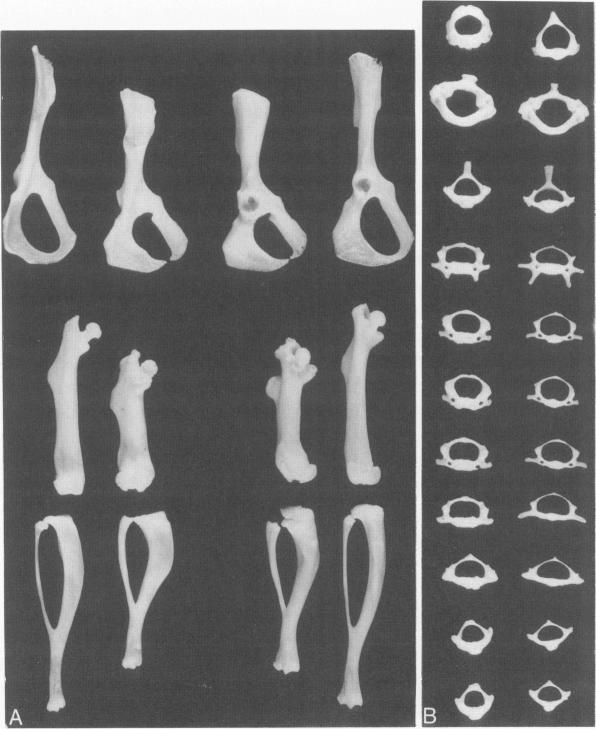

This report describes the clinical and pathologic alterations found in mice that have a recessively inherited, essentially complete deficiency of the lysosomal enzyme beta-glucuronidase. Affected animals have a shortened life span and are dysmorphic and dwarfed. Abnormal gait and decreased joint mobility correlate with glycosaminoglycan accumulation in articular tissue and cartilaginous and bony lesions result in extensive skeletal deformation. In these enzyme-deficient animals, lysosomes, distended by fine fibrillar and granular storage material, are particularly prominent in the macrophage system but also occur in other tissues including the skeletal and central nervous systems. The clinical and pathologic abnormalities in these mutant mice closely parallel those identified in humans with mucopolysaccharidoses (MPS). Therefore, these mice provide a well-defined genetic system for the analysis of the pathophysiology of mucopolysaccharidosis type VII, which has many features in common with the other MPS. The mutant mice provide an attractive animal model to test potential therapies for lysosomal storage disease.

本报告描述了在具有隐性遗传、溶酶体酶β-葡萄糖醛酸酶基本完全缺乏的小鼠中发现的临床和病理改变。患病动物寿命缩短,身体畸形且矮小。异常步态和关节活动度降低与关节组织中糖胺聚糖的积累相关,软骨和骨病变导致广泛的骨骼变形。在这些酶缺乏的动物中,被细纤维状和颗粒状储存物质扩张的溶酶体在巨噬细胞系统中尤为突出,但也出现在包括骨骼和中枢神经系统在内的其他组织中。这些突变小鼠的临床和病理异常与黏多糖贮积症(MPS)患者中发现的异常非常相似。因此,这些小鼠为分析VII型黏多糖贮积症的病理生理学提供了一个明确的遗传系统,该疾病与其他MPS有许多共同特征。这些突变小鼠为测试溶酶体贮积病的潜在治疗方法提供了一个有吸引力的动物模型。